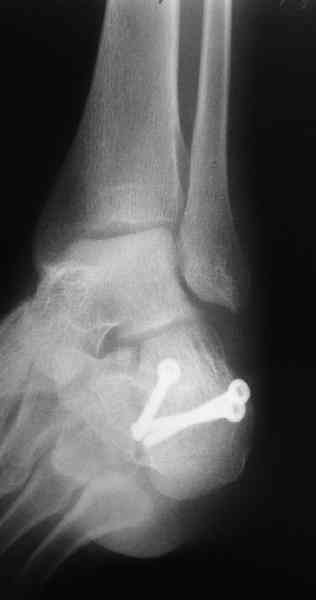

Пяточной пластиной

С уважением, А.Семенистый.

ГКБ № 13, Москва.

Какой предпочитаете доступ? Нет ли показательных рентгенснимков?

Открытый и закрытый способы лечения.

MOST OF MY COLLEGUES WOULD OPEN IT LATERALLY( a flap) and having a proper reduction would put a plate.

Перелом безусловно внутрисуставной. Киста-не киста принципиального значения не имеет.

Имея какой-то опыт остесинтеза пяточной кости пластинами пришли к выводу - где есть альтернатива лучше без нее, где нет значит пластина и долгие переживания в ожидании очередной перевязки. Может нам так не везло, но и одного некроза( слава богу без остеомеилита) достаточно, чтобы призадуматься.

Вправление задней фасеты с восстановлением таранно-пяточного угла возможно минимально-инвазивным методом Essex-Lopresti - под ЭОП или графическим контролем введенной в пяточный бугор толстой спицей или стрежнем Штеймана, которые служат рычагом. Для удержания вводим несколько тонких спиц Киршнера, фиксация в эквинусе.Подробнее в Margo anterior 1-2 2000\издание АО Матис в России, на сайте www.mathys.ru в архиве есть все выпуски. Метод внедрен у нас с 2000 года и дает неплохие результаты.